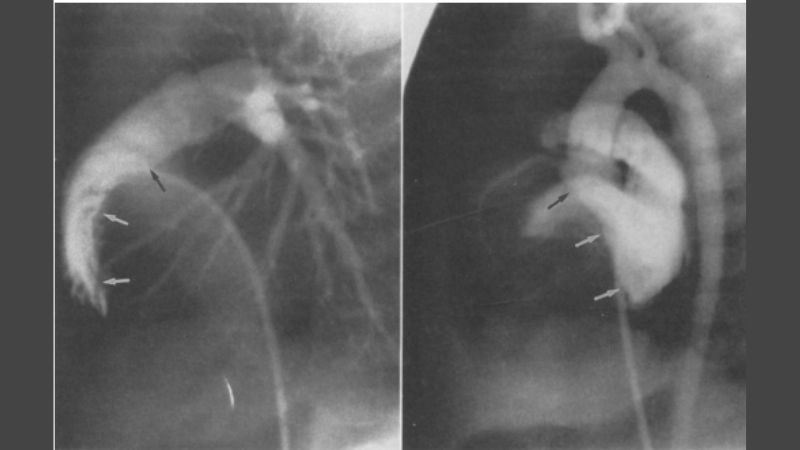

Images visual examples of cardiac fibroma

Cardiac fibroma is a rare, benign tumor of the heart composed mainly of fibrous tissue. It often develops in children and may cause symptoms related to heart rhythm and pumping function.